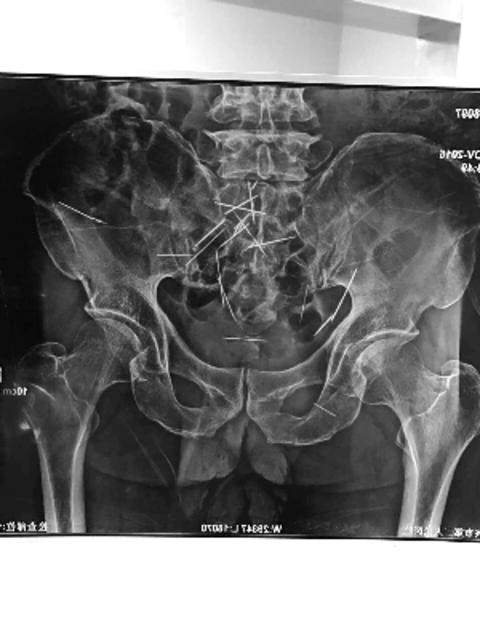

60多岁的妹妹匆匆赶回,带着朱贵到泰兴市人民医院做CT检查,结果发现,哥哥肚子里竟有22根绣花针。医生检查后发现,这些针可能已经在朱贵肚子里藏了几十年。

泰兴市人民医院普外科程医生介绍,从CT片上看,绣花针约有5厘米长,大部分附在腹腔壁上,其中有3根在腹腔很深的部位。“这些针在患者肚子里可能有几十年了。”

程医生介绍,因为绣花针数量太多,有些针已经跟腹腔组织长在一起,如何清除很是棘手。如果不处理,绣花针再发生移位,一旦戳破大血管,会有生命危险。